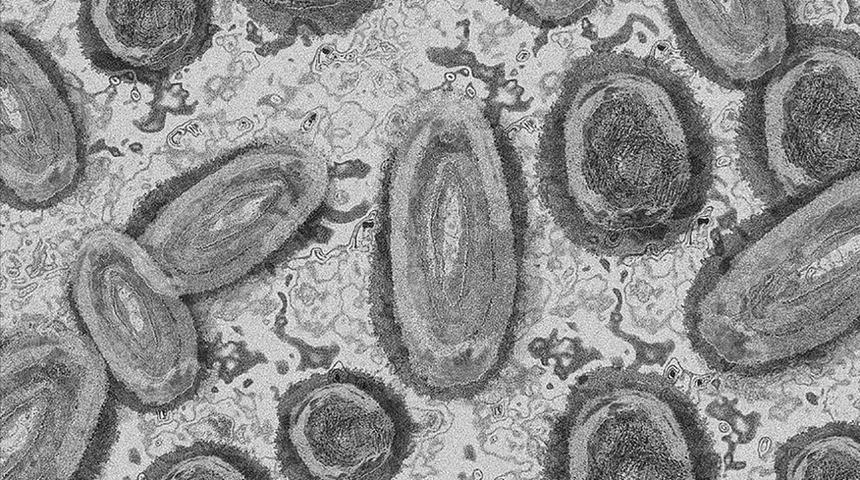

Maymun çiçeği virüsü, çift sarmallı bir DNA, zoonotik virüs ve Poxviridae ailesindeki Orthopoxvirus cinsinin bir türüdür. Variola (VARV), sığır çiçeği ve vaksinya virüslerini içeren insan ortopoks virüslerinden biridir. Çiçek hastalığının doğrudan atası ya da akrabası değildir ancak iki hastalığın benzer sonuçları vardır. Maymun çiçeği virüsünde hastalarda çiçek hastalığına göre daha hafif bir döküntü ve daha düşük ölüm oranı görülür.